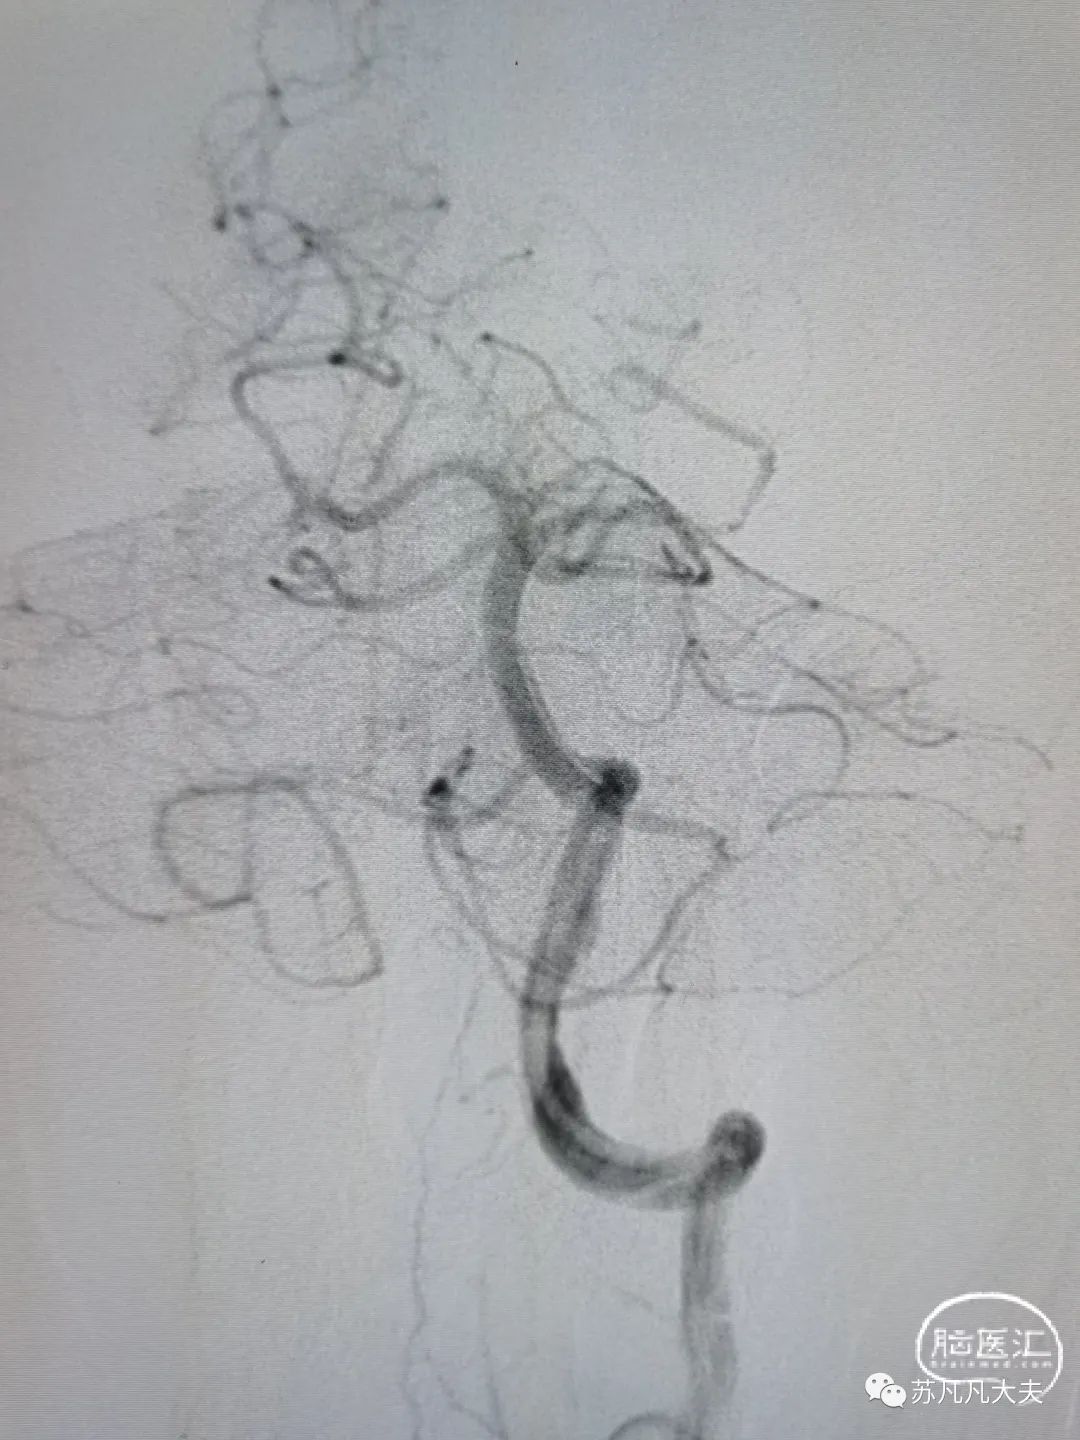

2.5/15球囊预扩后仍残余重度狭窄

4.5/13颅内支架定位,6atm释放

支架后颅内段狭窄解除